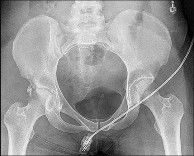

Question 18:

A 45-year-old female pedestrian is struck by a bus and presents hemodynamically unstable in the trauma bay. A pelvic radiograph shows a severely displaced anterior-posterior compression (APC-III) pelvic ring injury with a widened pubic symphysis. A pelvic binder is immediately applied to reduce pelvic volume. To maximize biomechanical efficacy and achieve optimal reduction of the symphysis, the binder should be centered exactly over which anatomic landmark?

Correct Answer: The greater trochanters

Explanation:

In the emergent management of open-book pelvic fractures (APC injuries), a pelvic binder or sheet must be centered directly over the greater trochanters of the femur. This placement efficiently translates compressive forces across the pelvic ring, closing the pubic symphysis and reducing pelvic volume to help tamponade venous and cancellous bone bleeding. Placing the binder too high (over the iliac crests) can paradoxically widen the pelvic outlet or fail to compress the true pelvis.